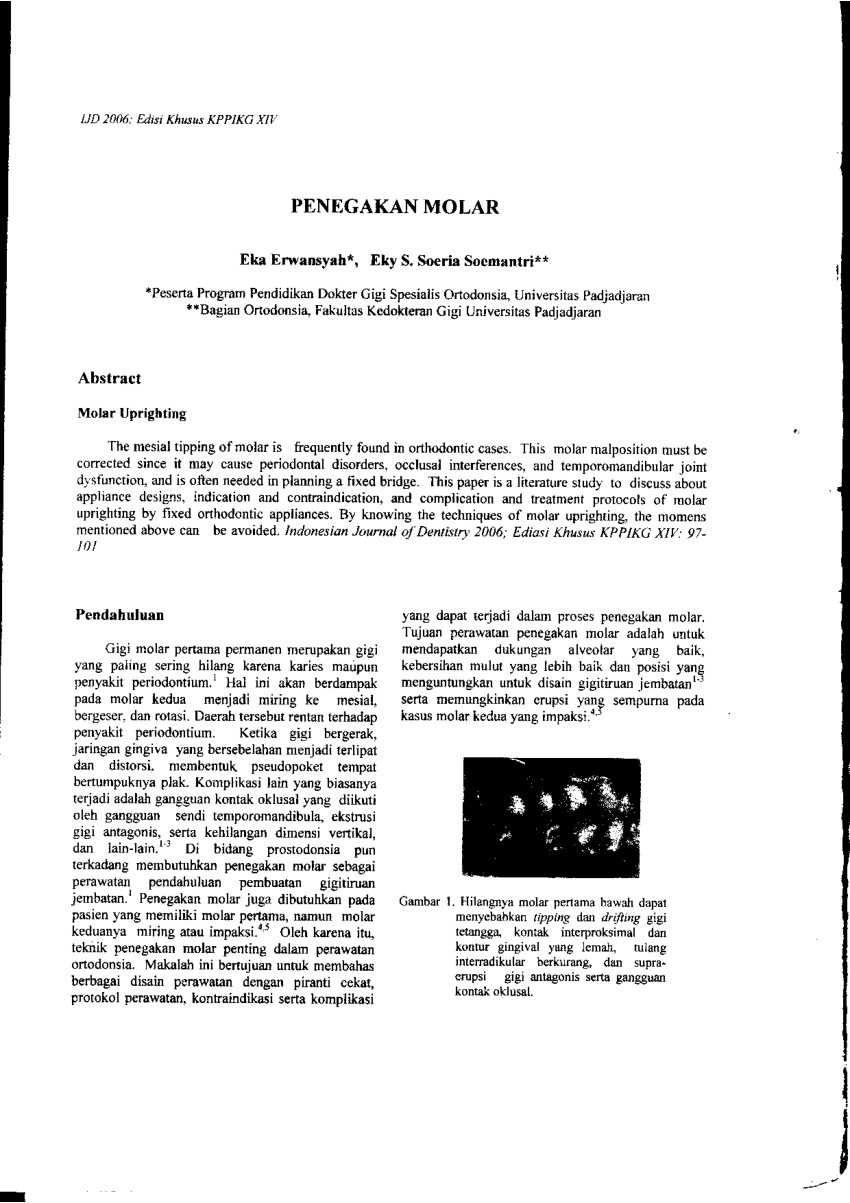

PDF) MOLAR UPRIGHTING